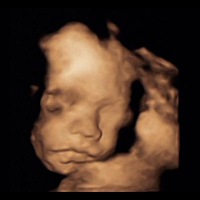

孕32周+0天